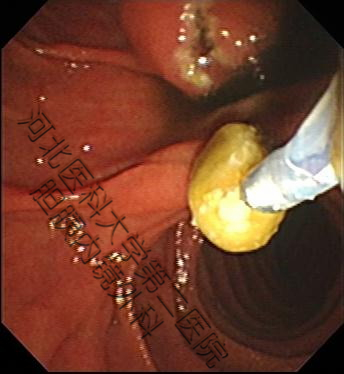

生活中并不缺少美,而是缺少发现美得眼睛,结石虽万恶,但具“自身美”,内镜下的结石也是“横看成岭侧成峰,奇形怪状各不同。簇拥颗粒如桑葚,表面圆滑似卵石。大如蜜枣小如豆,黑黄可见多半棕......”。接下来我们来一起欣赏百张内镜下取石的图片。(所见结石均已从胆总管取出,放入肠道内随大便排出)